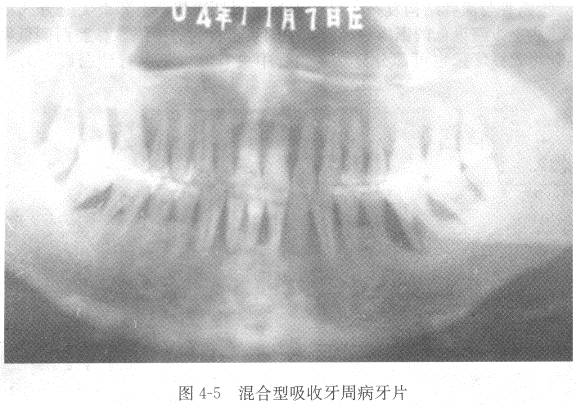

【答案】牙周病主要表现为牙槽骨的吸收破坏,X线片上的骨吸收主要有三种类型:(1)水平型吸收 一组牙齿或全口牙齿的牙槽骨从嵴顶向根尖方向呈水平向高度的减低(图4-3)。

(3)混合型吸收 牙槽骨既有水平吸收,又有垂直吸收(图4-5)。

【解析】X线表现 牙周炎主要表现为牙槽骨吸收,牙槽嵴顶及骨硬板模糊、消失,牙槽嵴高度降低。也可表现为牙周膜间隙增宽或缩窄、牙根吸收或牙骨质增生等。牙周炎所引起的牙槽骨吸收有三种类型:

③牙槽骨混合型吸收:牙槽骨广泛水平吸收,同时伴有个别或多数牙槽骨的垂直吸收。